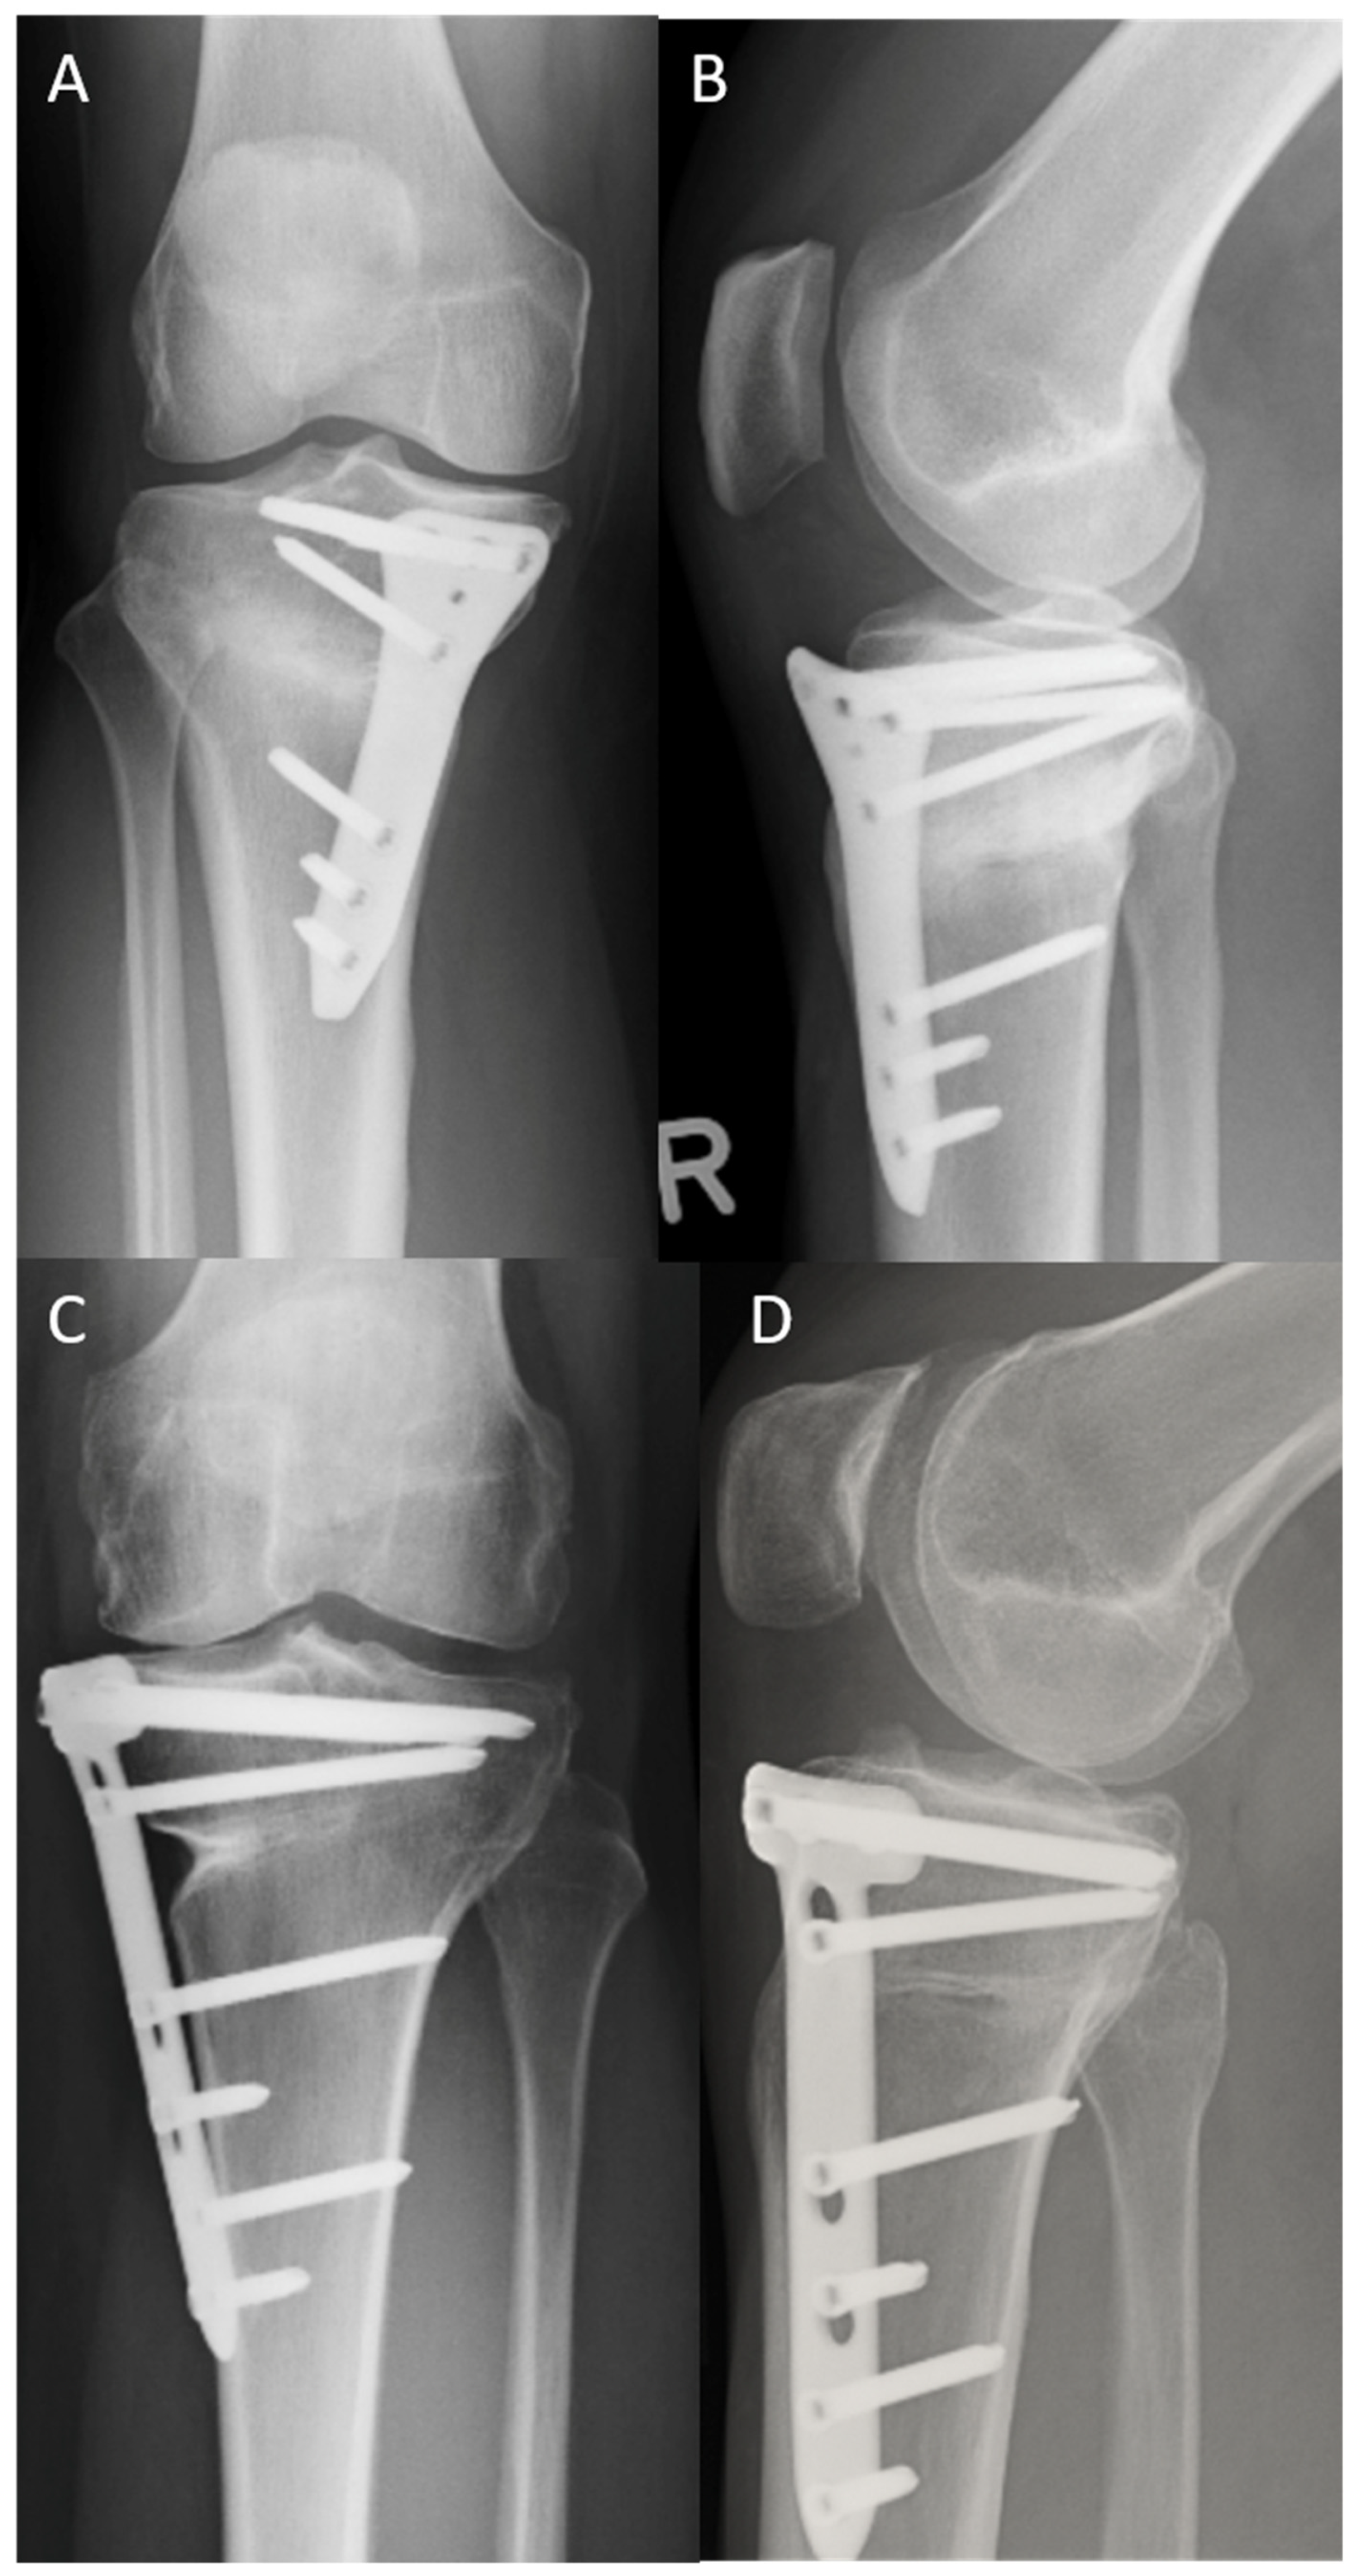

3.6. Rate, Cause, and Time of Implant Removal and Rate of Screws Jamming

Implant removal (Figure 5 and Figure 6) was performed at a mean of 16.8 months after surgery (minimum: 12 months, maximum: 20 months). In the TomoFix™ group, the plate was removed in 18 patients. In the LOQTEQ® HTO group, the implant was removed in 21 patients. This difference was not statistically significant (chi-square test, p ≥ 0.05). Fifteen patients in the TomoFix™ group and 13 patients in the LOQTEQ® HTO plate group reported discomfort as the cause of implant removal. This difference was also not statistically significant (chi-square test, p ≥ 0.05). The other patients reported no specific cause for the implant removal; they simply wanted it removed. In all patients, pain relief was reported. Screw jamming due to the cold welding of one or more rectangular screws was reported in eight surgical reports from the TomoFix™ group. No screw jamming was reported in the LOQTEQ® HTO group. The surgical time for the implant removal procedure in the LOQTEQ® HTO group was significantly shorter than in the TomoFix™ group (24.3 min ± 6.1 min vs. 36.8 min ± 14.9 min). This difference was statistically significant (U test, p ≥ 0.05).

Figure 5.

Post-operative X-rays before implant removal: (A) LOQTEQ® HTO plate (aap Implants, Berlin), knee a.p.; (B) LOQTEQ® HTO plate (aap Implants, Berlin), knee lateral; (C) TomoFix™ plate (Synthes, Switzerland) knee a.p.; (D) TomoFix™ plate (Synthes, Switzerland), knee lateral.